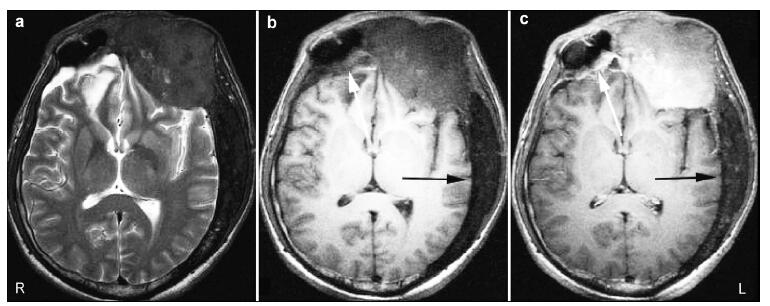

20161117201119  Figure 4 Axial MRI demonstrating abnormal thickening of the bones in a patient with FD. (a) T2-weighted images show the involved skull bones are hypointense. (b, c) T1-weighted images show the involved skull bones are hypointense (b) with varying enhancement (c). Left frontal bone and the wall of the right frontal sinus showed evident enhancement (white arrows) while the left posterior skull bones did not (black arrows).